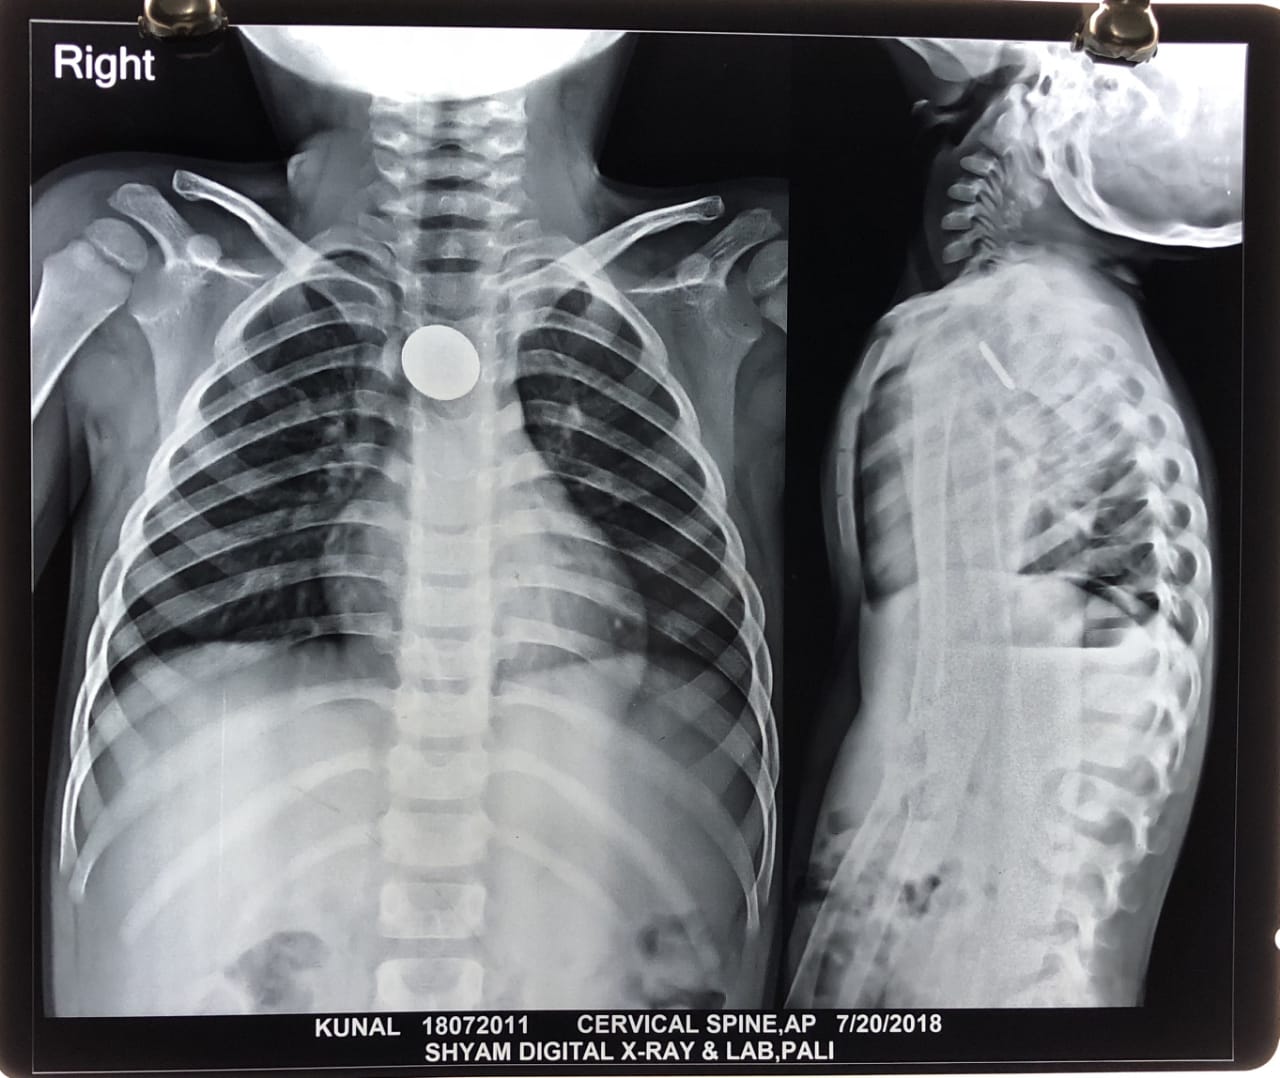

मासूम की भोजननली में फंसा रिमोट का सेल, ऑपरेशन कर निकाला

पाली. कई बार छोटे बच्चों द्वारा खेल-खेल में की गई लापरवाही उनकी जान के लिए आफत बन जाती है। ऐसा ही मामला शुक्रवार रात को बांगड़ मेडिकल कॉलेज हॉस्पिटल में सामने आया। एक 6 वर्षीय बालक ने रिमोट का सेल निकल लिया इससे बच्चे को खाने की नली में तेज दर्द की शिकायत शुरू हो गई। बच्चे को इमरजेंसी वार्ड में भर्ती किया गया। रात को ईएनटी विशेषज्ञ पहुंचे और शनिवार को बच्चे का ऑपरेशन करना तय किया। इसके तहत शनिवार को दूरबीन के माध्यम से तीन घंटे तक ऑपरेशन चला। इसके बाद बच्चे की भोजन नली में फंसे सेल को निकाला गया। चिकित्सकों ने बच्चे की हालत खतरे से बाहर बताई।

चिकित्सकों ने बताया कि महाराणा प्रताप नगर निवासी कुणाल पुत्र नारायण लाल ने सेल निगल लिया था। चिकित्सकों ने बताया कि बच्चों द्वारा सिक्के व अन्य वस्तुओं के निगलने के मामले तो कई बार सामने आए। लेकिन, ऐसा मामला अस्पताल में पहली बार आया था। बच्चे का सफल ऑपरेशन मेडिकल कॉलेज हॉस्पिटल के ईएनटी विभाग की टीम डॉ. एएन योगी, डॉ. कमलेश, डॉ. राघवेंद्रसिंह, रामचंद्र चौधरी व घनश्यामसिंह ने किया।

चिकित्सकों ने बताया कि सिक्के निगलने पर बच्चे को इतना खतरा नहीं होता है। लेकिन, सेल निगलने से बच्चे को काफी खतरा था। सेल बच्चे की भोजन नली में फट जाता तो उसमें भरा रसायन बच्चे की भोजन नली को खराब कर सकता था। इससे बच्चे की जान को भी खतरा हो सकता था।

- बच्चे खेलते समय नासमझी में बार कोई चीज नगल जाते है। यह मामला भी वैसा ही था। लेकिन, रिमोट सेल निगलने से बच्चे को खतरा काफी ज्यादा था। टीम ने दूरबीन के माध्यम से ऑपरेशन किया। यह अस्पताल का पहला ऑपरेशन था। बच्चा पूरी तरह से स्वस्थ है।

- डॉ. एएन योगी, इएनटी विशेषज्ञ, बांगड़ मेडिकल कॉलेज हॉस्पिटल, पाली